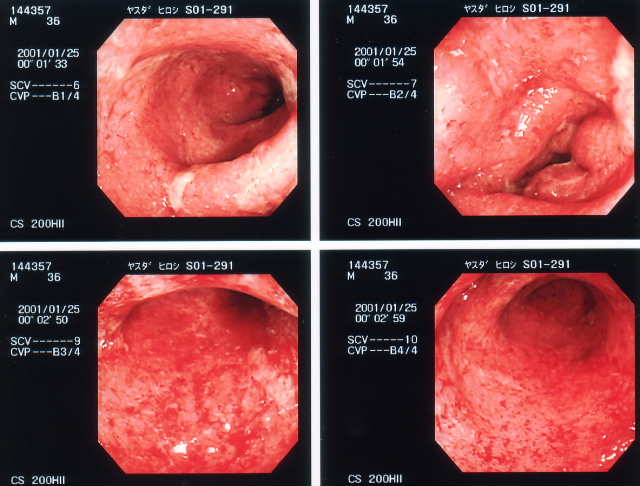

2001/1/25 直腸鏡   直腸からS状結腸までの様子。まだ、かなり下血していた時で、全体に赤や白の炎症がかなり目立つ。